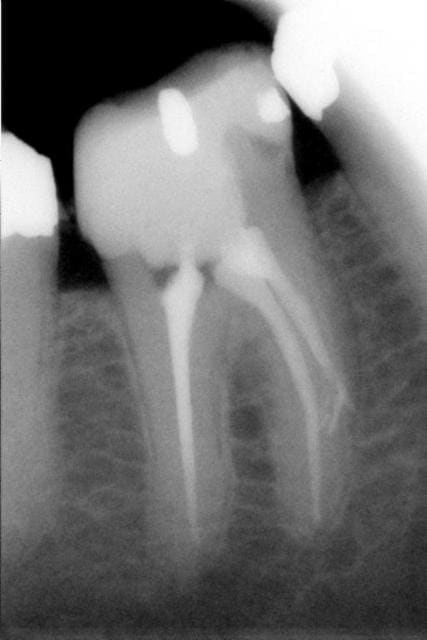

Voici un cas de fracture compacteur.

Utiliser un mac spaden dans ce genre de cas était une bêtise.

Aprés beaucoup d'efforts pour perméabliser les 2 cannaux et les préparer, c'est trop dommage de gacher le résultat en cassant un compacteur.

Cela ne m'a pas gêné pour desobturer et faire l'empreinte pour l'inlay-core, mais la condensation de la gutta au niveau apical n'a pas été terrible.

C'est d'ailleurs un des cas qui m' a décidé à utiliser de temps en temps le thermafill.